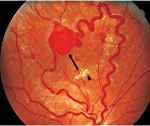

Q85 Факоматозы, не классифицированные в других рубриках